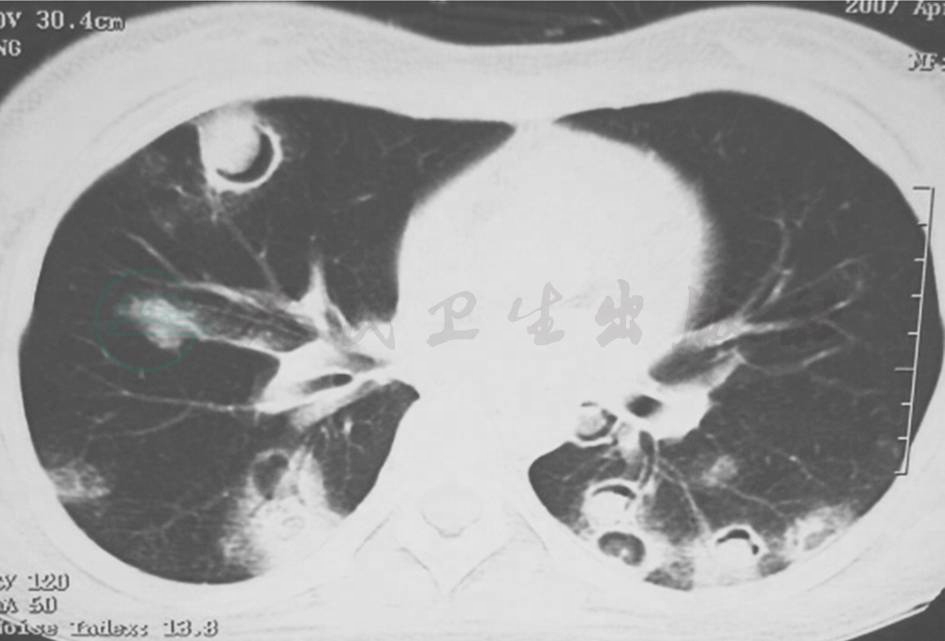

发病第4天,患者于当地医院就诊,胸部CT提示双肺多发结节样改变(图1)。

图1 发病第4天胸部CT表现